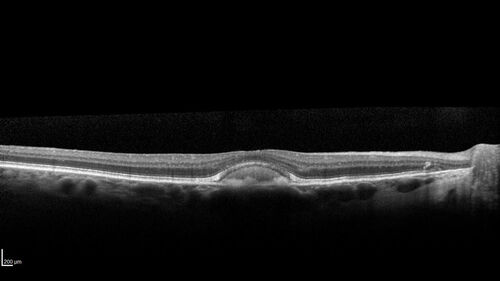

Dry Macular Degeneration with Pseudodrusen and vitelliform lesion

80 year old female with 20/50 vision in both eyes. Mild blurring